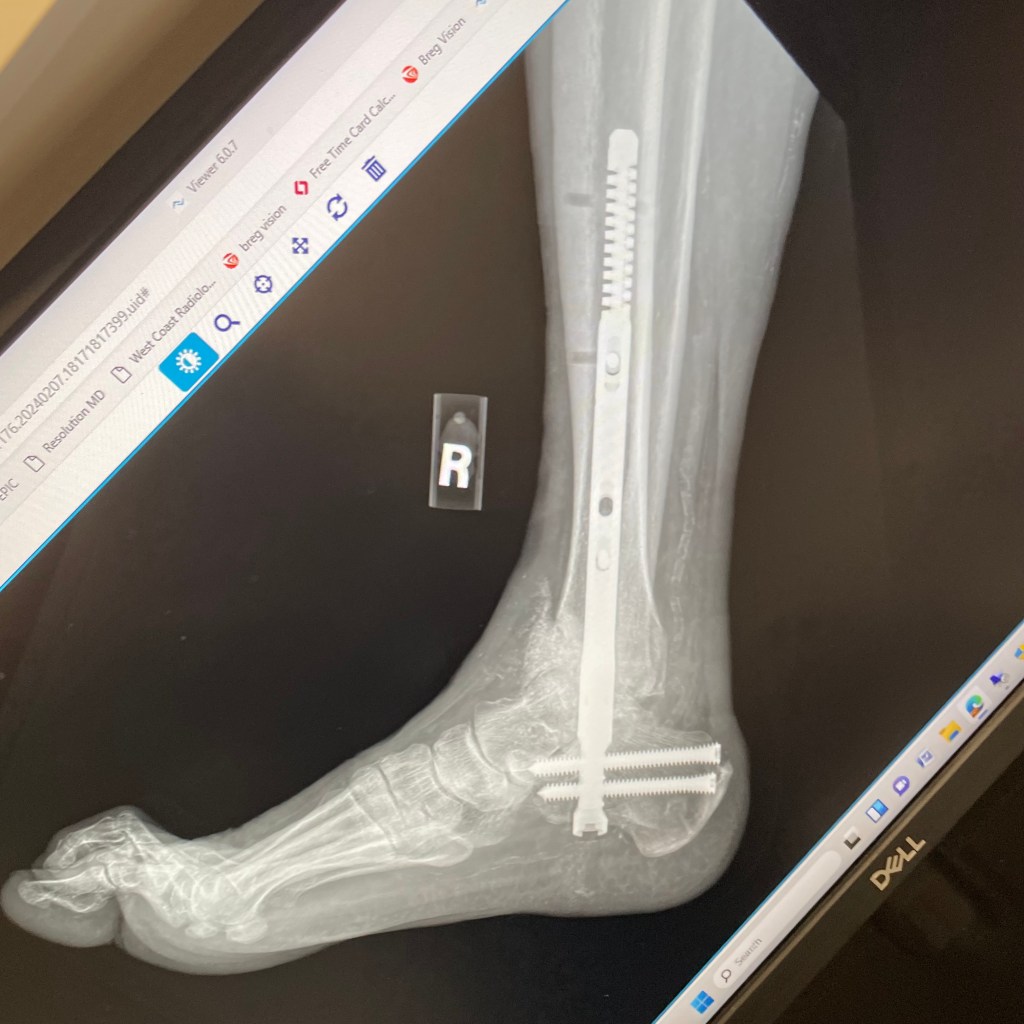

Here are some x-rays of my foot:

From top left to bottom, the dates are:

• February 7, 2024

• April 22, 2024

• May 13, 2024

• Today, May 20, 2024

You can see clearly that my ankle is dislocating downwards in the front. There is a growing hole right before you get to the toe bones. The problem was apparent on the May 13th x-ray, but much more obvious today. The other ankle surgeon at the office, a church friend, said that the bone is softer/weaker due to Charcot Foot, and usually that causes dislocations, fractures, and bone disintegration. By giving me another non-weight bearing cast, they hope to stabilize the ankle, and have it try to heal on its own.

Based on my luck so far, that is not likely. I will probably need more surgeries, including external fixators on the foot/ankle again. In the meantime, we are still waiting for another CT scan to get more clarity on what is happening.